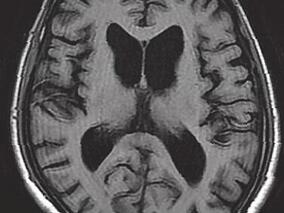

1小时条评论【病例资料】 患者,女性,32岁,医师。因左侧肢体麻木5个月,右侧肢体无力12天,于2005年6月3日收入北京医院神经外科。 现病史:患者于5个月前(2005年1月17日)无明显诱因出现左侧肢体麻木,无力弱、头痛、发热,在当地医院行头颅CT检查未见明显异常,予灯盏花素...